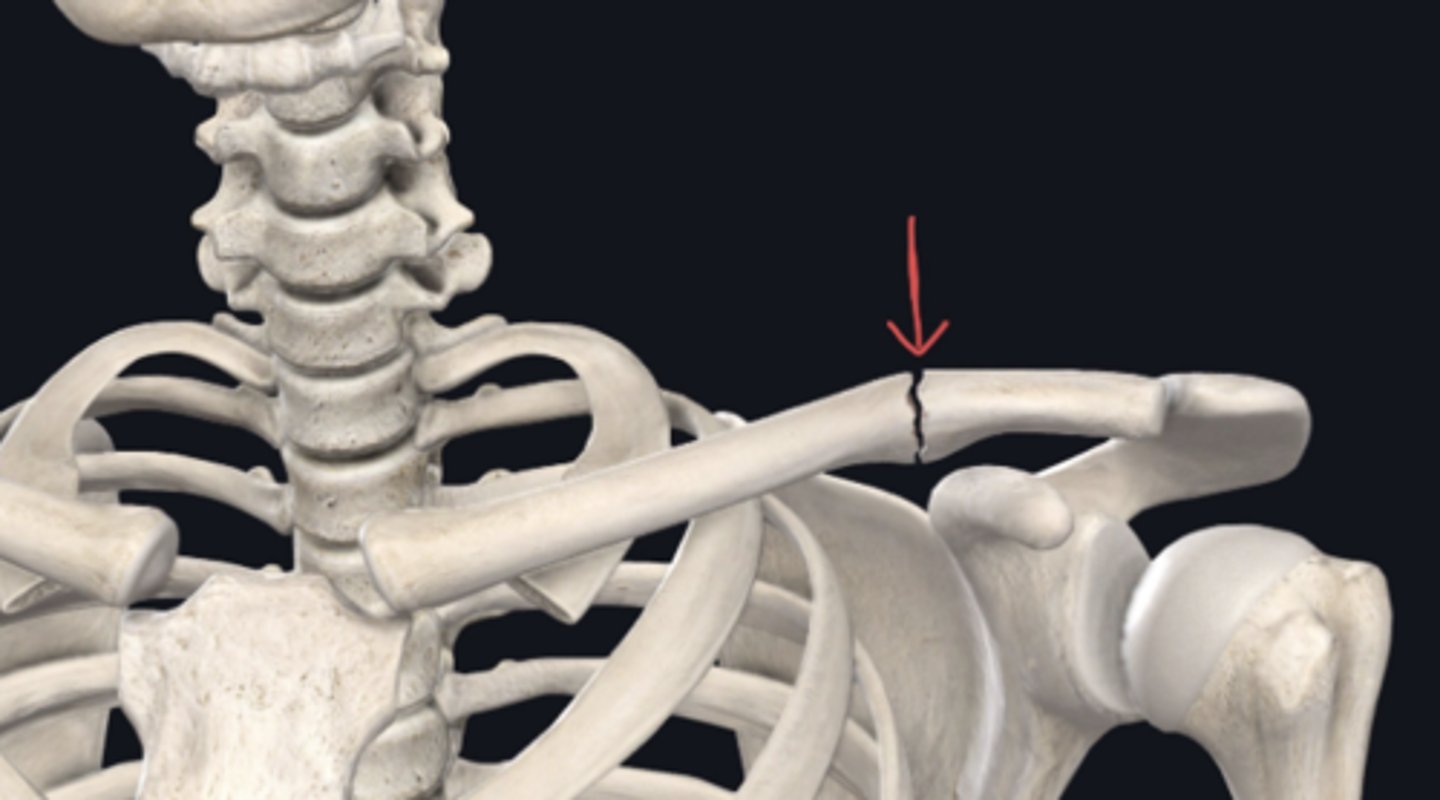

Sagittal (longitudinal also correct)

Identify the plane of section in which the indicated fracture has occurred. (Free response)